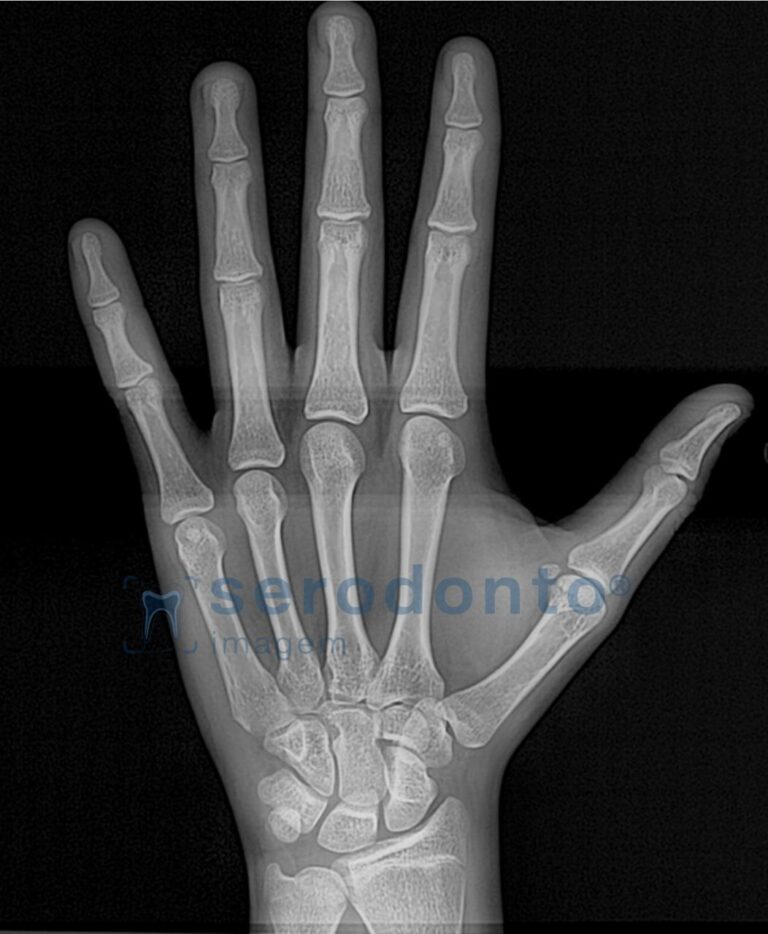

Radiografia Carpal

A radiografia carpal é utilizada para avaliar a idade óssea, auxiliando no planejamento de tratamentos ortodônticos e cirúrgicos.